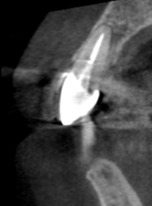

- 治療後

歯科用CTによる精密検査

精密根管治療では、事前に3次元CTを用いた立体的な診断を行います。保険診療では基本的に2次元のレントゲンでの確認となり、精度に差が生まれます。